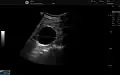

Renal cyst as seen on abdominal ultrasound -